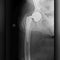

Titanium hip implants snapped in hundreds of people, took years before some products recalled

In part two of our investigation with partner site KFF Health News, CBS News' Anna Werner looks into why it took years for some products to be recalled despite breaking inside hundreds of people's bodies.